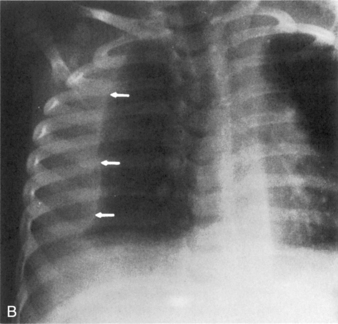

If the film is obtained during expiration, the heart will appear larger and less well defined. The lung fields will appear to be hazier and the pulmonary vascular markings more prominent. Hypoinflation of the lung fields can lead to misinterpretation of the images and misdiagnosis of a basilar pneumonia or cardiomegaly. Furthermore, if maximal inspiration is not present, the lungs can appear more congested and the trachea will appear to buckle to the right.21,24 Figure 10-2 illustrates these differences with two views obtained from a normal child during inspiration and expiration.

image

Fig. 10-2 Inspiratory and expiratory chest radiograph. Normal chest films obtained from the same child during inspiration and expiration. A, Inspiratory phase. Nine ribs can be counted above the diaphragm, indicating good inspiration. Alignment is good (note similarity of clavicles). Penetration of film is good (all vertebral bodies are visible; some pulmonary vascular markings can be seen). Intercostal spaces are equal; both sides of the diaphragm are visible. The mediastinum and trachea are straight (arrows). Heart borders are sharply defined, and heart size is normal. Pulmonary vascular markings are visible in the proximal two thirds of lung fields (normal). B, Expiratory phase. Only eight ribs are visible above the diaphragm (see numbers on ribs), indicating inadequate lung expansion. Alignment is good. Penetration of film is good. Intercostal spaces are narrow because expiration is occurring. Both sides of the diaphragm are hazy, and the left hemidiaphragm is not readily identifiable. The mediastinum appears widened, and the trachea seems to buckle to the right (arrows). Heart appears much larger than in A, and the heart borders are obliterated, but this is caused by expiration and reduction in apparent lung volume. Silhouette sign appears to be present, cardiothoracic size calculated from this view would be large, and pulmonary vascular markings appear prominent, but these are all artifacts caused by expiration.

(Courtesy H. Rex Gardner, Rush Presbyterian Saint Luke’s Hospital, Chicago, IL.)